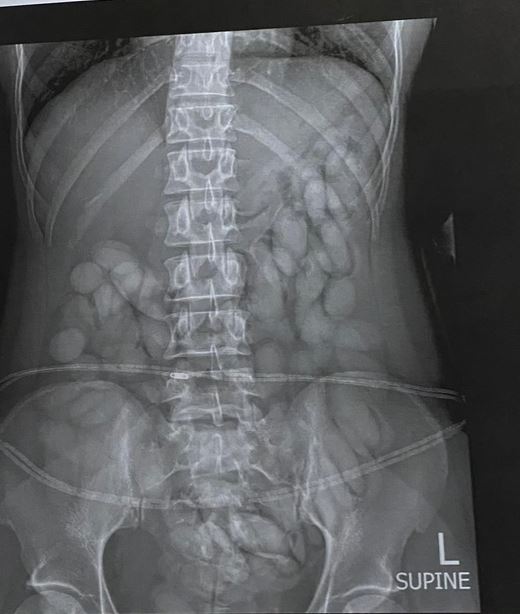

“The team immediately intercepted the drug mule as she was making her way through immigration. She was immediately arrested, and taken to a local hospital where a medical X-ray confirmed and detected foreign objects in her stomach,” said Mathe.

On Sunday evening, Mathe said the process to release the suspected drugs from her body was underway.

“She has already released more than 60 bullets of suspected cocaine thus far. She is currently under police guard and custody,

” said Mathe.